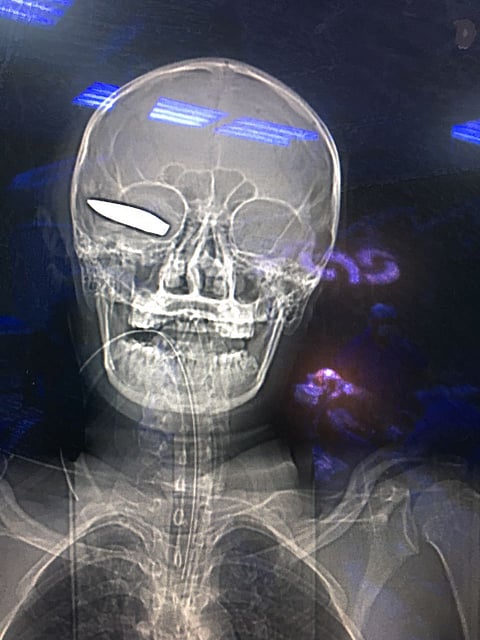

تمكّن طبيب جراحة المخ والأعصاب بمستشفى الملك فهد المركزي بجازان الدكتور إسماعيل العسلي، مع فريقه الطبي المكون من أخصائيي التخدير والأشعة والعمليات والتمريض؛ من استخراج مقذوف أصاب رأس أحد جنود التحالف العربي باليمن.

وذكر الطبيب المعالج أن المصاب وصل إلى قسم الطوارئ في حالة غيبوبة تامة؛ نتيجة الإصابة التي تعرض لها بالرأس.

وقال "العسلي": أدخلنا المصاب إلى قسم العمليات، وتم استخراج المقذوف من الرأس، وإدخال المصاب قسم العناية المركزة بشكل مؤقت لحين استقرار حالته الصحية.

وأضاف: بدأت الحالة في التماثل للشفاء، ثم غادر المصاب المستشفى، وتتم متابعة حالته عبر العيادات الخارجية.